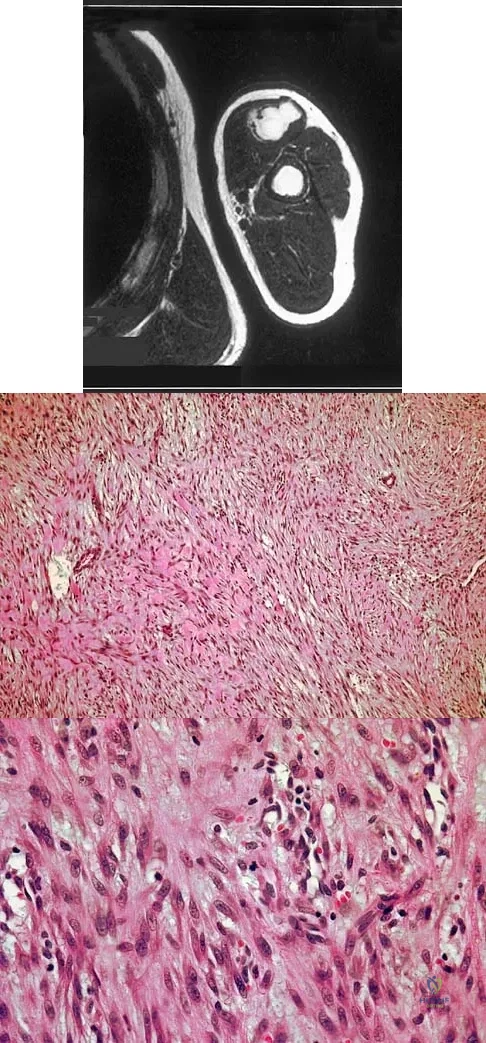

The parents of a previously healthy 3-year-old child report that she refused to walk on awakening. Examination later in the day reveals that the patient can walk but with a noticeable limp. She has a temperature of 99.5 degrees F (37.5 degrees C). Range of motion measurements are shown in Figure 50. An AP pelvis radiograph is normal. Laboratory studies show a WBC count of 9,000/mm3 and an erythrocyte sedimentation rate of 10 mm/h. Management should consist of